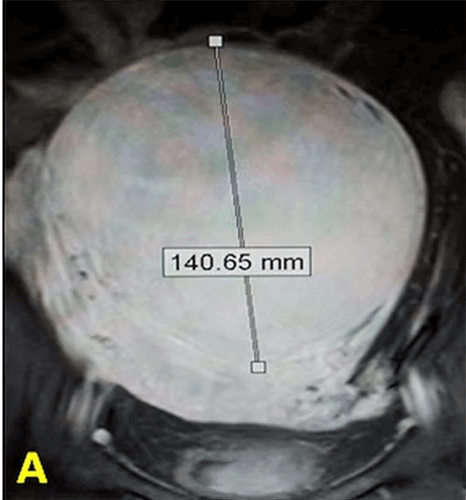

In our patient with a large uterine fibroid, embolization (UFE) was performed. After the procedure, the fibroid underwent complete necrosis and its diameter was reduced from 140mm to 70mm, while the normal uterine tissue remained viable.